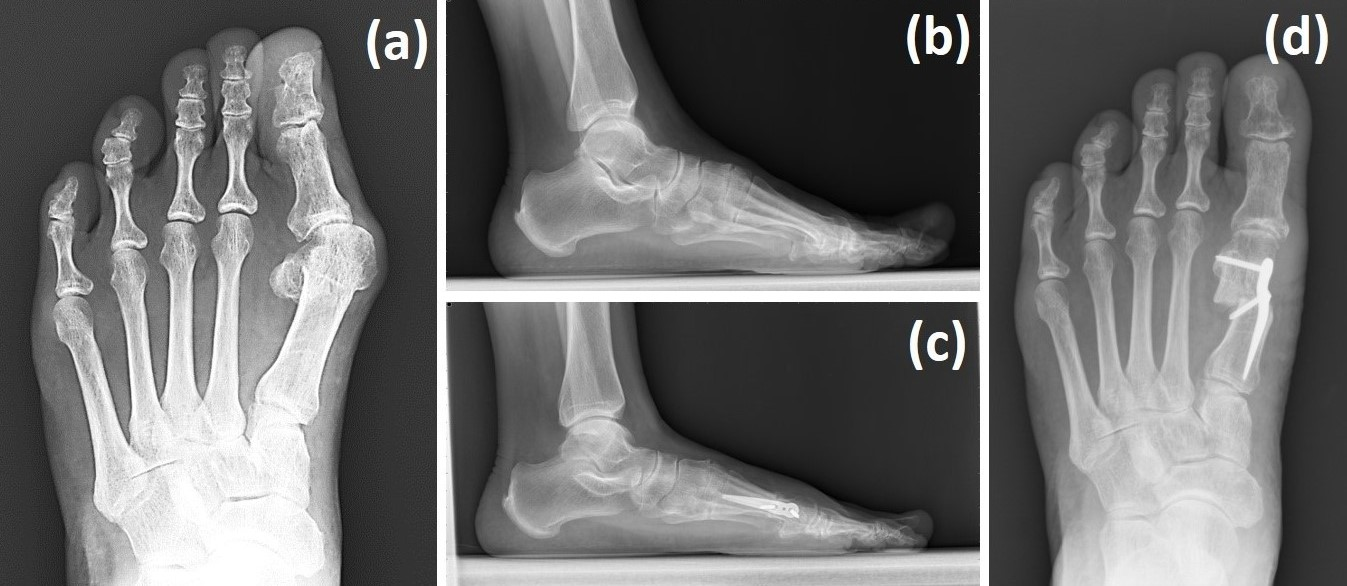

At our institution, the senior surgeon employs a targeted step-wise algorithm incorporating the Spear plate (Aplus Biotechnology Company, New Taipei City, Taiwan), Wilson osteotomy, and/or distal soft tissue balancing depending on preoperative findings (Figure 1).

Figure 1. HV revision surgery performed using the Spear plate with Wilson osteotomy combined with a distal soft tissue procedure. The left foot of a 63-year-old male patient with HV recurrence was corrected, as shown in the above weight-bearing radiographs. (a,b) Preoperative radiographs and (c,d) 3-month-postoperative radiographs.